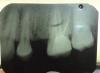

Book Опубликовано 6 июня, 2011 Поделиться Опубликовано 6 июня, 2011 Добрый день. Помогите, пожалуйста. Сильные боли в правой верхней челюсти. Врачи говорят, что все в порядке. На снимках ничего им не видно. Я думаю, что болит 16, но точно сказать не могу. Боли усиливаются к ночи, днем ноет, но терпимо. 16 вскрывали, прочистили каналы, поставили пломбу, боли не прошли. Меня направили к эндодонтисту, чтобы еще раз прочистил все каналы, это стоит дорого и я не знаю, поможет ли это лечение. Мой стоматолог сказал, если эндодонтист не поможет, тогда на резекцию верхушки корня. Скажите, пожалуйста, что вы видите на снимке. Могут ли быть боли от 7-ки? Стоит ли идти к эндодонтисту или лучше удалить зуб и поставить имплантат. Не знаю уже к кому обратиться. Спасибо.P.S. Прилагаю снимки, не знаю, на каком лучше видно. Ссылка на комментарий

Book Опубликовано 6 июня, 2011 Автор Поделиться Опубликовано 6 июня, 2011 Похоже на невралгию II ветви тройничного нерва...Конечно терапевты могут сказать еще о 4 канале в 6 зубе... В общем нужна полноценная диагностика чтобы избавиться от проблемы. Т.е проблема может быть не в зубах... Вы из какого города? Скажите, пожалуйста, а 4 канал судя по снимку не найден и не прочищен? правильно я понимаю, потому что стоматолог, который чистил каналы, сказал, что все нашел, а эндодонтист говорит, что 4 ый не найден, я не знаю, стоит ли соглашаться на поиски четвертого, вдруг не поможет. Я живу в Германии Ссылка на комментарий

Aldo Rain Опубликовано 6 июня, 2011 Поделиться Опубликовано 6 июня, 2011 4 канала может и не быть, на дентальной компьютерной томографии его можно было бы лицезреть я думаю. А что было с 5 зубом, почему удалили? И почему депульпировали 6? Какие были жалобы, опишите подробнее немного Ссылка на комментарий